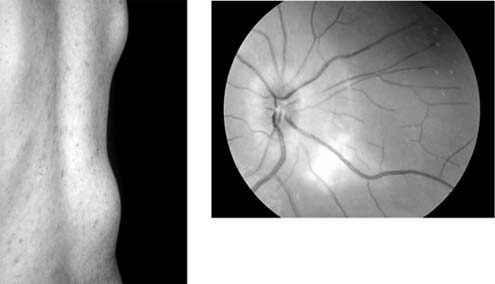

Figure 15-24: Tuberculosis. Cold abscess. A young man presented with a swelling on his back (left) and a choroidal lesion (right). Aspiration of the abscess revealed Mycobacterium tuberculosis.

Tuberculosis of the Uveal Tract